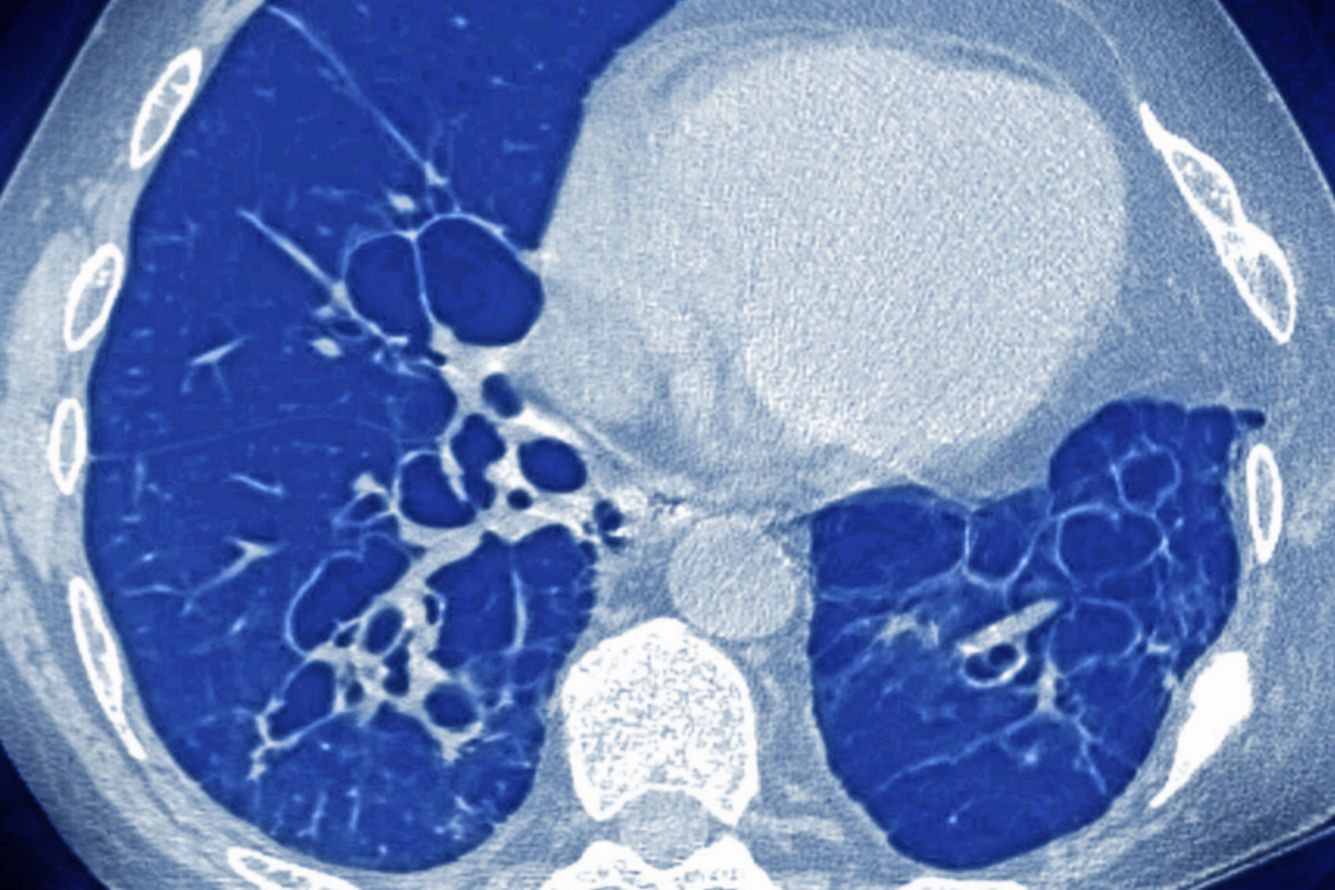

Муковисцидоз — это генетическое заболевание, при котором в разных органах накапливается густая слизь, что, в частности, мешает дышать и вызывает предрасположенность к инфекциям.